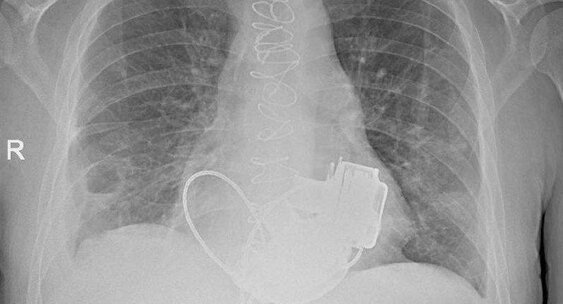

Уникальный пациент, которому впервые в России имплантировали сразу два искусственных желудочка сердца, готовится к выписке из Мариинской больницы в Санкт-Петербурге.